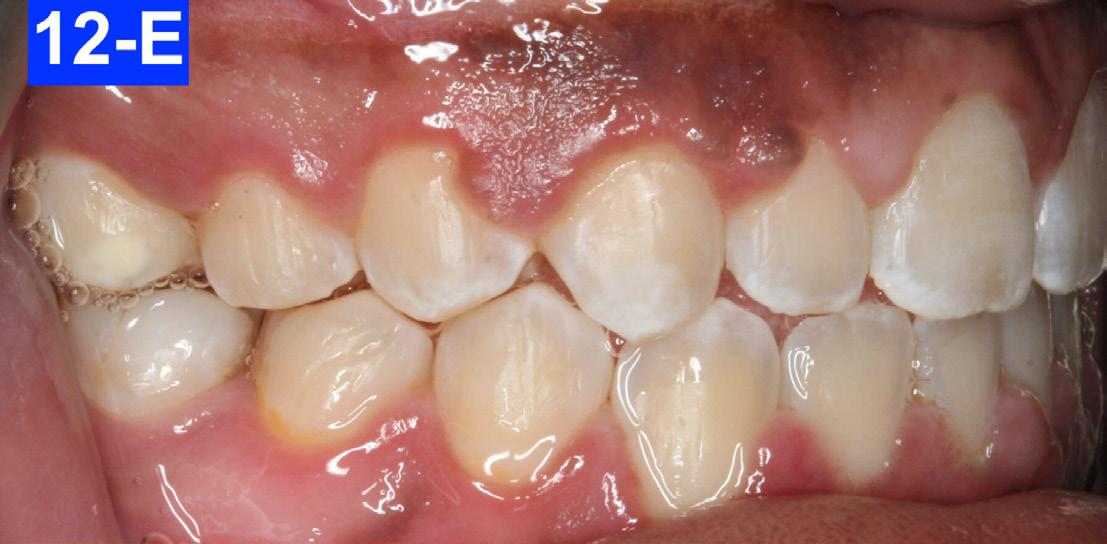

Clinical Micro-esthetic appraisal revealed a full Angle Class I molar and cuspid relationship. The arches were wide, there was generalized spacing in the anterior region. The patient had 2.0 mm overjet and -3.0 mm overbite. Maxillary lateral incisors appeared to be microdonts (Figures 4-A, B, C, D).

Fig. 4-B: Pre-treatment, right lateral view

Fig. 4-C: Pre-treatment, left lateral view